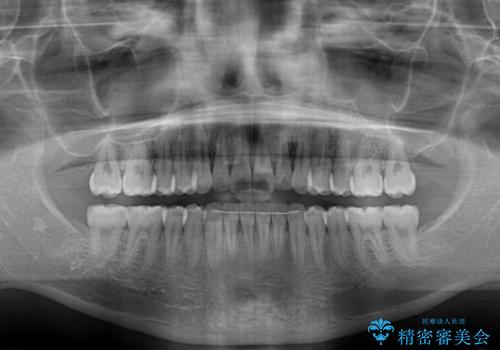

前歯のクロスバイト インビザラインによる矯正治療

- 上下のクロスバイトと前歯のデコボコを気にして来院された患者様です。

インビザラインを用い、IPR(歯と歯の間を削る)と歯列全体を拡大させることで、歯並びを整えていくこととしました。

治療を急いでいらっしゃらなかったため、のんびりと治療を進めていきました。3年以上の期間を要しましたが、きれいな口元に仕上がりました。